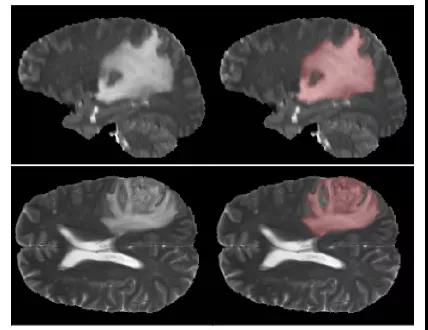

为了评估我们的网络性能,我们使用BRATS18脑瘤分割数据集。它包含175名恶性胶质瘤和低级别恶性胶质瘤患者的MRI扫描。图像分辨率为240×240×155像素。ground truth标签是由神经放射学专家创建的。数据集的一个示例如图2所示。

图2:MRI切片的例子以及分割的ground truth